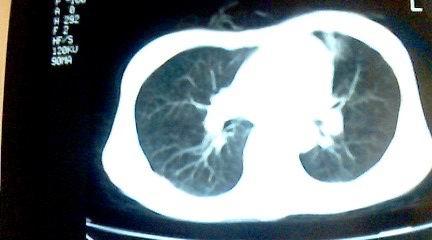

标题: CT25218:请教!胸部CT,胸8椎体骨质破坏,伴周围软组织肿。 [打印本页]

标题: CT25218:请教!胸部CT,胸8椎体骨质破坏,伴周围软组织肿。

患者,女41岁,肢体乏力。

双肺及胸椎结核。

两肺上叶继发性肺结核;胸椎结核并椎旁寒性脓肿形成。